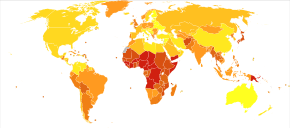

Pneumonia affects approximately 450 million people globally (7% of the population) and results in about 4 million deaths per year.[12][13] Pneumonia was regarded by William Osler in the 19th century as "the captain of the men of death".[14] With the introduction of antibiotics and vaccines in the 20th century, survival improved.[12] Nevertheless, in developing countries, and among the very old, the very young, and the chronically ill, pneumonia remains a leading cause of death.[12][15] Pneumonia often shortens suffering among those already close to death and has thus been called "the old man's friend".[16]

Pneumonia is a common illness affecting approximately 450 million people a year and occurring in all parts of the world.[12] It is a major cause of death among all age groups resulting in 4 million deaths (7% of the world's total death) yearly.[12][13] Rates are greatest in children less than five, and adults older than 75 years.[12] It occurs about five times more frequently in the developing world than in the developed world.[12] Viral pneumonia accounts for about 200 million cases.[12] In the United States, as of 2009, pneumonia is the 8th leading cause of death.[20]

Children

In 2008, pneumonia occurred in approximately 156 million children (151 million in the developing world and 5 million in the developed world).[12] In 2010, it resulted in 1.3 million deaths, or 18% of all deaths in those under five years, of which 95% occurred in the developing world.[12][19][93] Countries with the greatest burden of disease include India (43 million), China (21 million) and Pakistan (10 million).[94] It is the leading cause of death among children in low income countries.[12][13] Many of these deaths occur in the newborn period. The World Health Organization estimates that one in three newborn infant deaths is due to pneumonia.[95] Approximately half of these deaths can be prevented, as they are caused by the bacteria for which an effective vaccine is available.[96] In 2011, pneumonia was the most common reason for admission to the hospital after an emergency department visit in the U.S. for infants and children.[97]